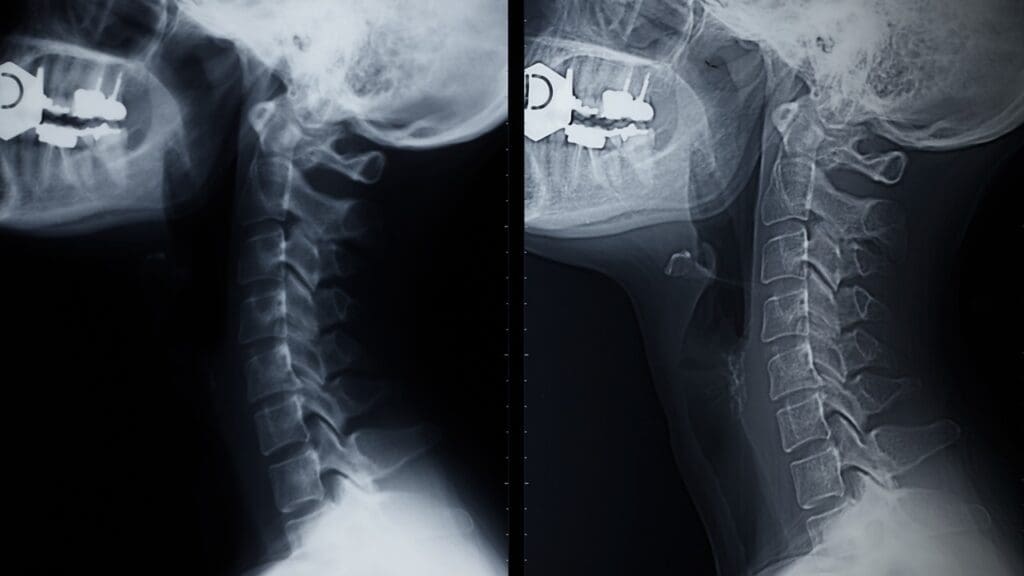

Cervical Disc Replacement

This surgery is for the neck. It’s great for those with neck disc problems. It keeps the neck moving, which helps avoid future problems.

“Cervical disc replacement has shown promising results in maintaining spinal mobility and reducing symptoms in patients with cervical degenerative disc disease.”

Cervical Artificial Disc Replacement

Cervical artificial disc replacement is a non-fusion option. It replaces the damaged disc with an artificial one. This allows for natural movement and might lower the risk of future problems. Studies have shown promising results with this method, making it a good alternative to fusion.